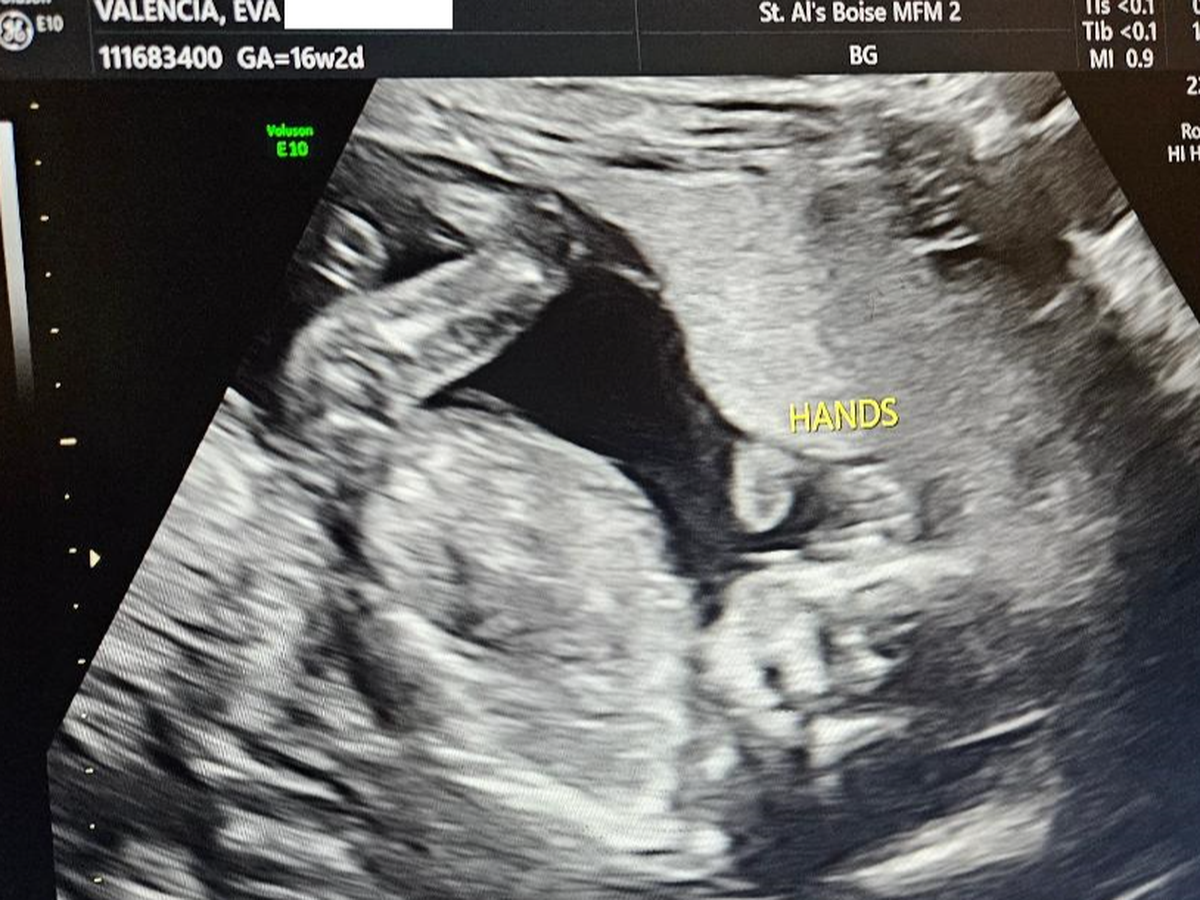

My Wife Eva and I are expecting our 5th child. We were given some devastating news. Eva was diagnosed with something called "placenta accreta" along with a "previa placenta". Eva’s cervix is also smaller than usual.

Eva was seen by two fetal medicine doctors here and it has been recommended that we fly to The University of Utah Hospital’s MFM (Maternal Fetal Medicine) clinic in Salt Lake City. We will be doing this on Tuesday June 10th with an appointment on Wednesday June 11th with the premier doctor in all of the United States of America for these specific types of conditions. Per the Boise Idaho doctor’s, it was advised that we stay and live in Utah, close to the clinic for the duration of the pregnancy. The thinking behind all of this is both to keep Eva and the baby close to the Hospital in the event of an emergency, so both of them can be attended to quickly by the best doctors and surgeons in the country for this situation. The hope though is that Eva can make it to 32 weeks and have the baby at that time. We have been informed that the baby, regardless of birth time, will spend a good amount of time in the NICU. If Eva has an emergency then both she and the baby will be there much longer. In this scenario we were told months, not weeks, of a hospital stay for both the baby and Eva. Of course we are praying for her and the baby to make it to 32 weeks so both of them come out of this together, healthy. Eva is currently 16 weeks.